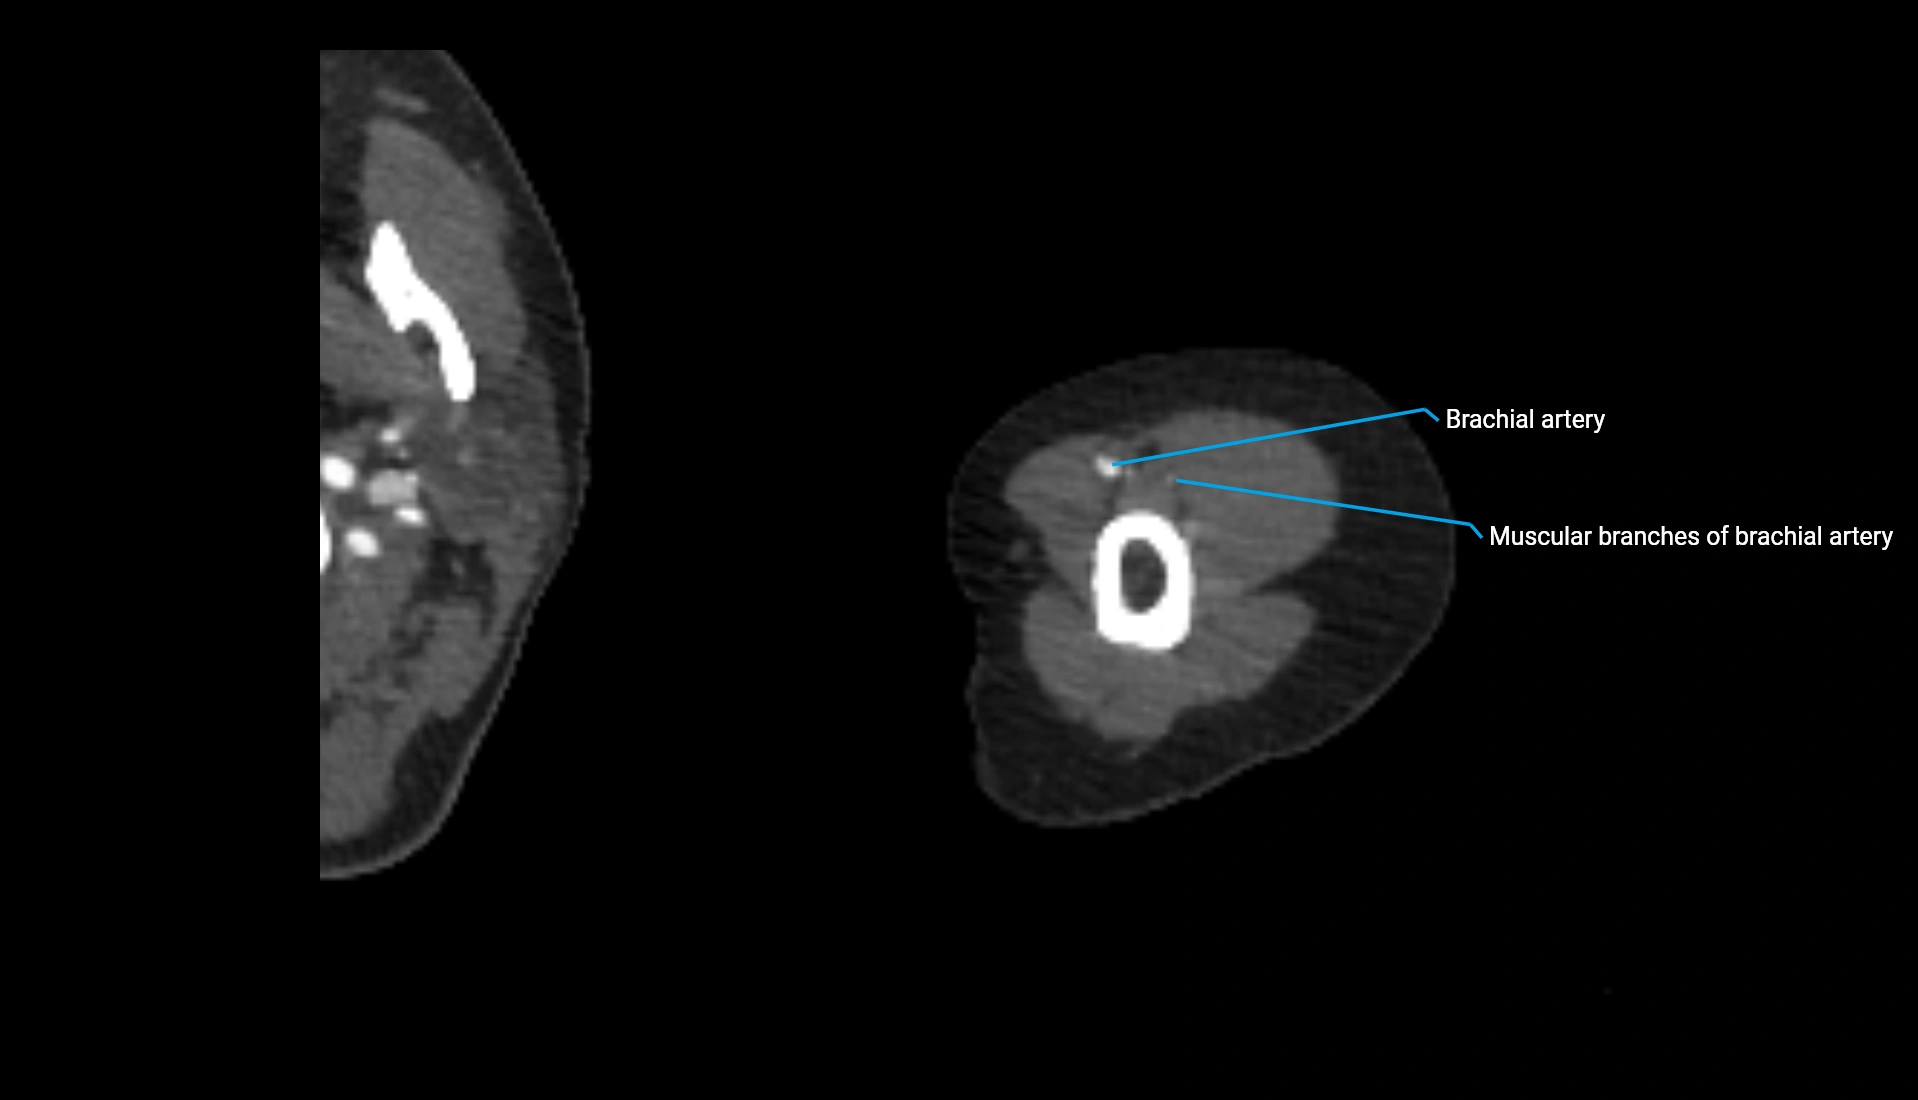

CT Appearance

Non-Contrast CT:

• Cortex: High-density, sharply defined

• Subchondral bone: Dense cancellous matrix

• Articular surface: Smooth concave contour articulating with the capitellum

• Excellent for evaluating bone integrity, alignment, and subtle fractures